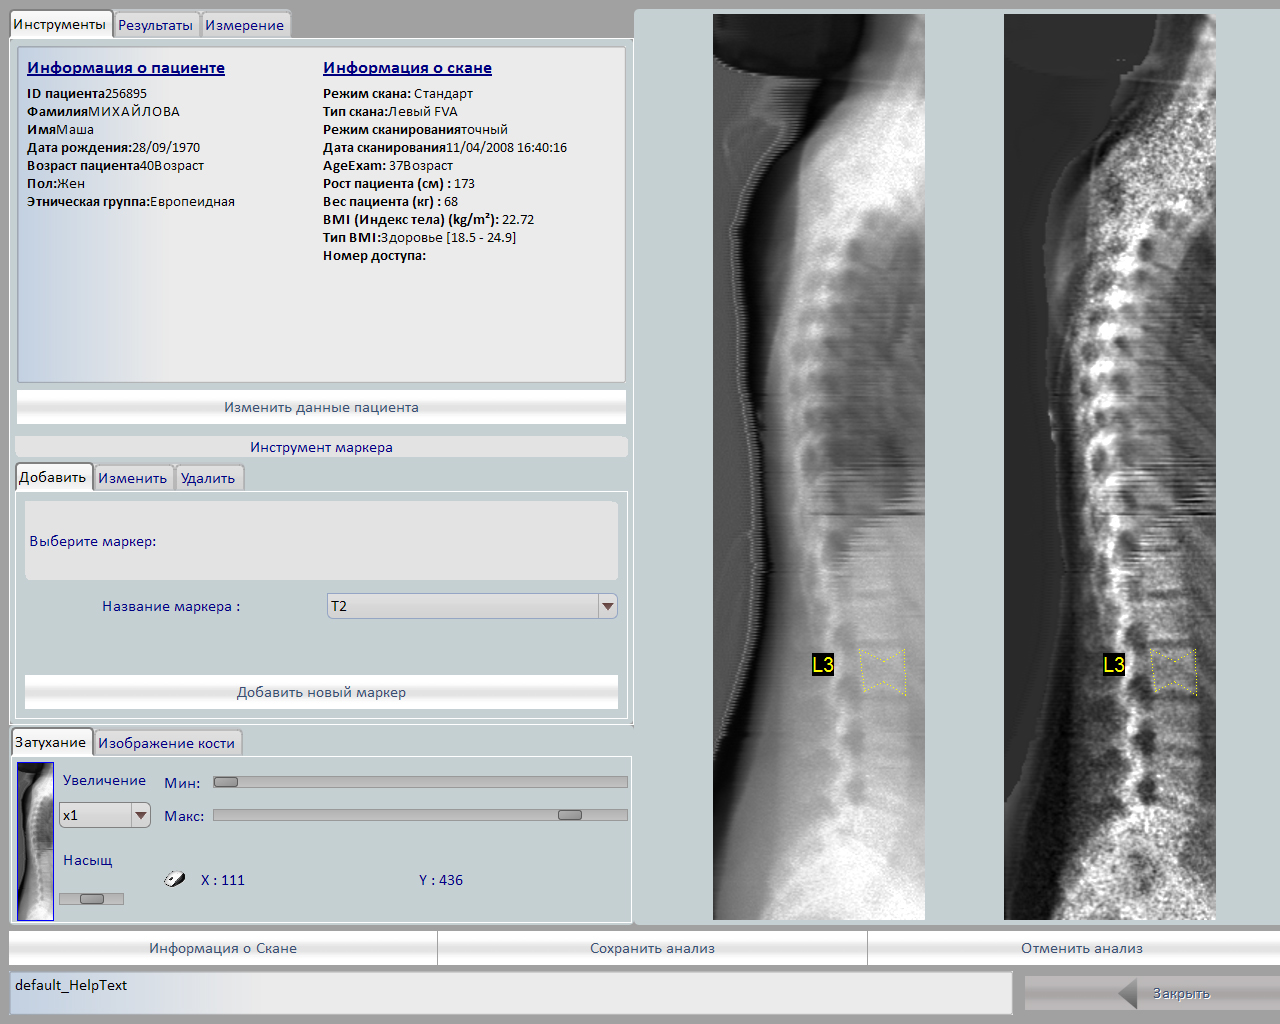

Метод DXA, двухэнергетическая рентгеновская абсорбциометрия, или денситометрия, отражающая содержание гидроксиапатита на единицу поверхности костной ткани (двойная энергия), корректирует рассеивающие эффекты двумерного сенсора. Методика двухэнергетической рентгеновской абсорбциометрии признана «золотым стандартом» в диагностике, поскольку она сочетает в себе ряд выгодных качеств; возможность исследования осевого скелета, хорошая чувствительность и специфичность, высокая точность и низкая ошибка воспроизводимости, низкая доза облучения, относительная дешевизна, быстрота исследования. При латеральном сканировании позвоночника возможен автоматизированный морфометрический анализ позвонков для выявления деформационных изменений.

Главной особенностью аппарата является широкий спектр возможных исследований: поясничный отдел позвоночника, проксимальный отдел бедренной кости, кость предплечья, обследование позвоночника в боковой проекции, боковая проекция оценки позвонков, возможность проводить исследования состава тела.

- Высокое качество визуализации, позволяющее исследовать изменения формы позвонков в латеральной проекции